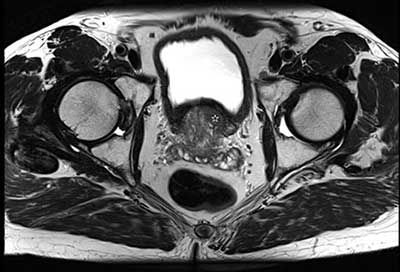

Figure 1

Axial T2-WI of the prostate in a 66-year-old man with PSA of 10 ng/ml. Far anteriorly and cranially on the left side in the transition zone of the prostate there is an ill-defined marked low-signal intensity area (white star) with irregular contour, suspicious for prostate cancer.